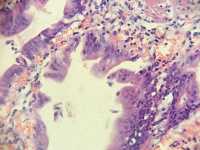

胆囊长8直径3.2囊壁粗糙

图2

慢性胆囊炎

同意,黏膜上皮增生,少数有轻度非典型性。